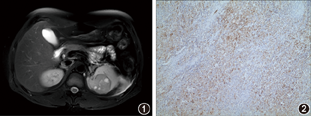

患者,男,34岁。2019年4月6日因腰背部酸痛不适伴全程无痛性肉眼血尿3 d入院。查体:左肾区压痛、叩痛(+)。既往史:2年前因右肾结石行输尿管软镜碎石术。家族中无类似病史,无特殊遗传病史。尿常规:红细胞计数1 961.6个/μL,尿微量白蛋白80 mg/L,肌酐128.4μmol/L。β2微球蛋白2.85 mg/L,超声检查:左肾4.6 cm×4.3 cm低回声,形态规则、境界清,内部回声不均,CDFI示内部血流不明显。CT检查:左肾上极直径约4.8 cm类圆形软组织密度影,CT值约30 HU,边界尚清,增强后轻度不均匀强化,皮质期CT值45 HU,排泄期53 HU,局部肾盂及肾盏受压。MRI检查:病灶为不规则团块样T1WI等低、T2WI稍高信号灶,大小约5.4 cm×4.2 cm,实性为主伴小囊状长T1长T2信号影,增强扫描皮质期边缘轻度强化,髓质期及排泄期轻中度强化,肿块内侧缘突出于肾轮廓外、局部包膜似不连续,左肾周脂肪间隙局部模糊信号不均,局部包膜破裂伴左肾周筋膜水肿(图1)。术前诊断左肾恶性肿瘤T4N0M0期。考虑患者腰痛与肿物出血坏死有关。全麻下行腹腔镜根治性左肾切除术,术中见肿物局部破裂伴少量出血,并与周围筋膜粘连。术后病理检查,大体标本见左肾上极一大小5.0 cm×3.5 cm×3.0 cm肿块,剖面灰白、灰红、灰黄色,实性质中,紧邻被膜,剖面见一囊,最大径0.5 cm,内含灰绿色胶冻样物。镜下观察以梭形细胞为主,组织病理倾向肾滑膜肉瘤(synovial sarcoma,SS)。免疫组化染色检查:Vimentin(+++)、CKpan(++)(图2)、CK7(+)、BCL-2(+)、Ki-67(40%~50%+)。将病理结果送至复旦大学附属肿瘤医院会诊(编号:T2019-12250)并行基因检测,会诊意见倾向为梭形细胞滑膜肉瘤,基因检测结果示t(18q11.2)(SYT):(+),即有SYT基因相关异位。PET-CT检查未见其他组织来源滑膜肉瘤。最终诊断为原发性肾滑膜肉瘤。术后予以抗感染、补液治疗,患者无腰酸、腰痛等并发症,无血尿。术后50 d行脂质体阿霉素化疗6个疗程,术后5个月行重离子放疗(碳离子60 GyE/15Fx)15 d。术后随访14个月,未见肿瘤复发和转移。